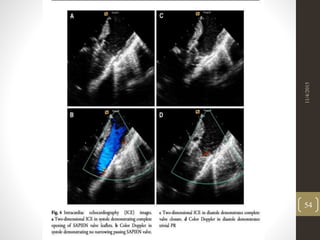

11/4/2015

54

• 52.

• 53.

• 54.